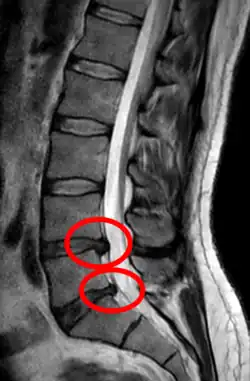

- Magnetic resonance imaging is the gold standard study for confirming a suspected LDH. With a diagnostic accuracy of 97%, it is the most sensitive study to visualize a herniated disc due to its significant ability in soft tissue visualization. MRI also has higher inter-observer reliability than other imaging modalities. It suggests disc herniation when it shows an increased T2-weighted signal at the posterior 10% of the disc. Degenerative disc diseases have shown a correlation with Modic type 1 changes. When evaluating for postoperative lumbar radiculopathies, the recommendation is that the MRI is performed with contrast unless otherwise contraindicated. MRI is more effective than CT in distinguishing inflammatory, malignant, or inflammatory etiologies of LDH. It is indicated relatively early in the course of evaluation (<8 weeks) when the patient presents with relative indications like significant pain, neurological motor deficits, and cauda equina syndrome. Diffusion tensor imaging is a type of MRI sequence used for detecting microstructural changes in the nerve root. It may be beneficial in understanding the changes that occur after herniated lumbar disc compresses a nerve root, and might help in differentiating the patients that need surgical intervention. In patients with a high suspicion of radiculopathy due to lumbar disc herniation, yet the MRI is equivocal or negative, nerve conduction studies are indicated.[44] T2-weighted images allow for clear visualization of protruded disc material in the spinal canal.

-

MRI scan of cervical disc herniation between C5 and C6 vertebrae -

MRI scan of cervical disc herniation between C6 and C7 vertebrae -

MRI scan of large herniation (on the right) of the disc between L4 and L5 vertebrae -

A rather severe herniation of the L4–L5 disc -

Example of a herniated disc at L5–S1 in the lumbar spine